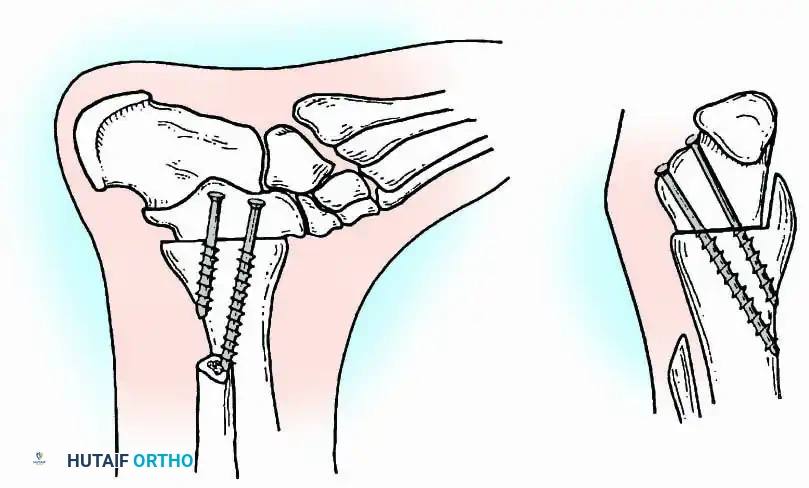

Internal fixation is currently the preferred method for uncomplicated ankle arthrodesis due to higher union rates, superior patient comfort, and the elimination of pin-tract infections. Biomechanical studies demonstrate that crossed, large-diameter (6.5 mm or 7.3 mm) cannulated cancellous screws provide exceptional resistance to shear and torsional forces.

A standard construct involves two or three screws:

1. A "home run" screw directed from the posterior malleolus into the anterior neck of the talus.

2. A screw from the medial malleolus into the lateral body of the talus.

3. A screw from the anterolateral tibia into the medial talar body.

In cases of severe osteopenia or when extending the fusion to the subtalar joint (Tibiotalocalcaneal Arthrodesis), retrograde intramedullary nailing provides a load-sharing construct with superior bending stiffness.

For complex hindfoot reconstructions, specialized plating systems, including anterior or lateral locking plates, can be utilized to supplement screw fixation, particularly when structural allografts are required to restore limb length.